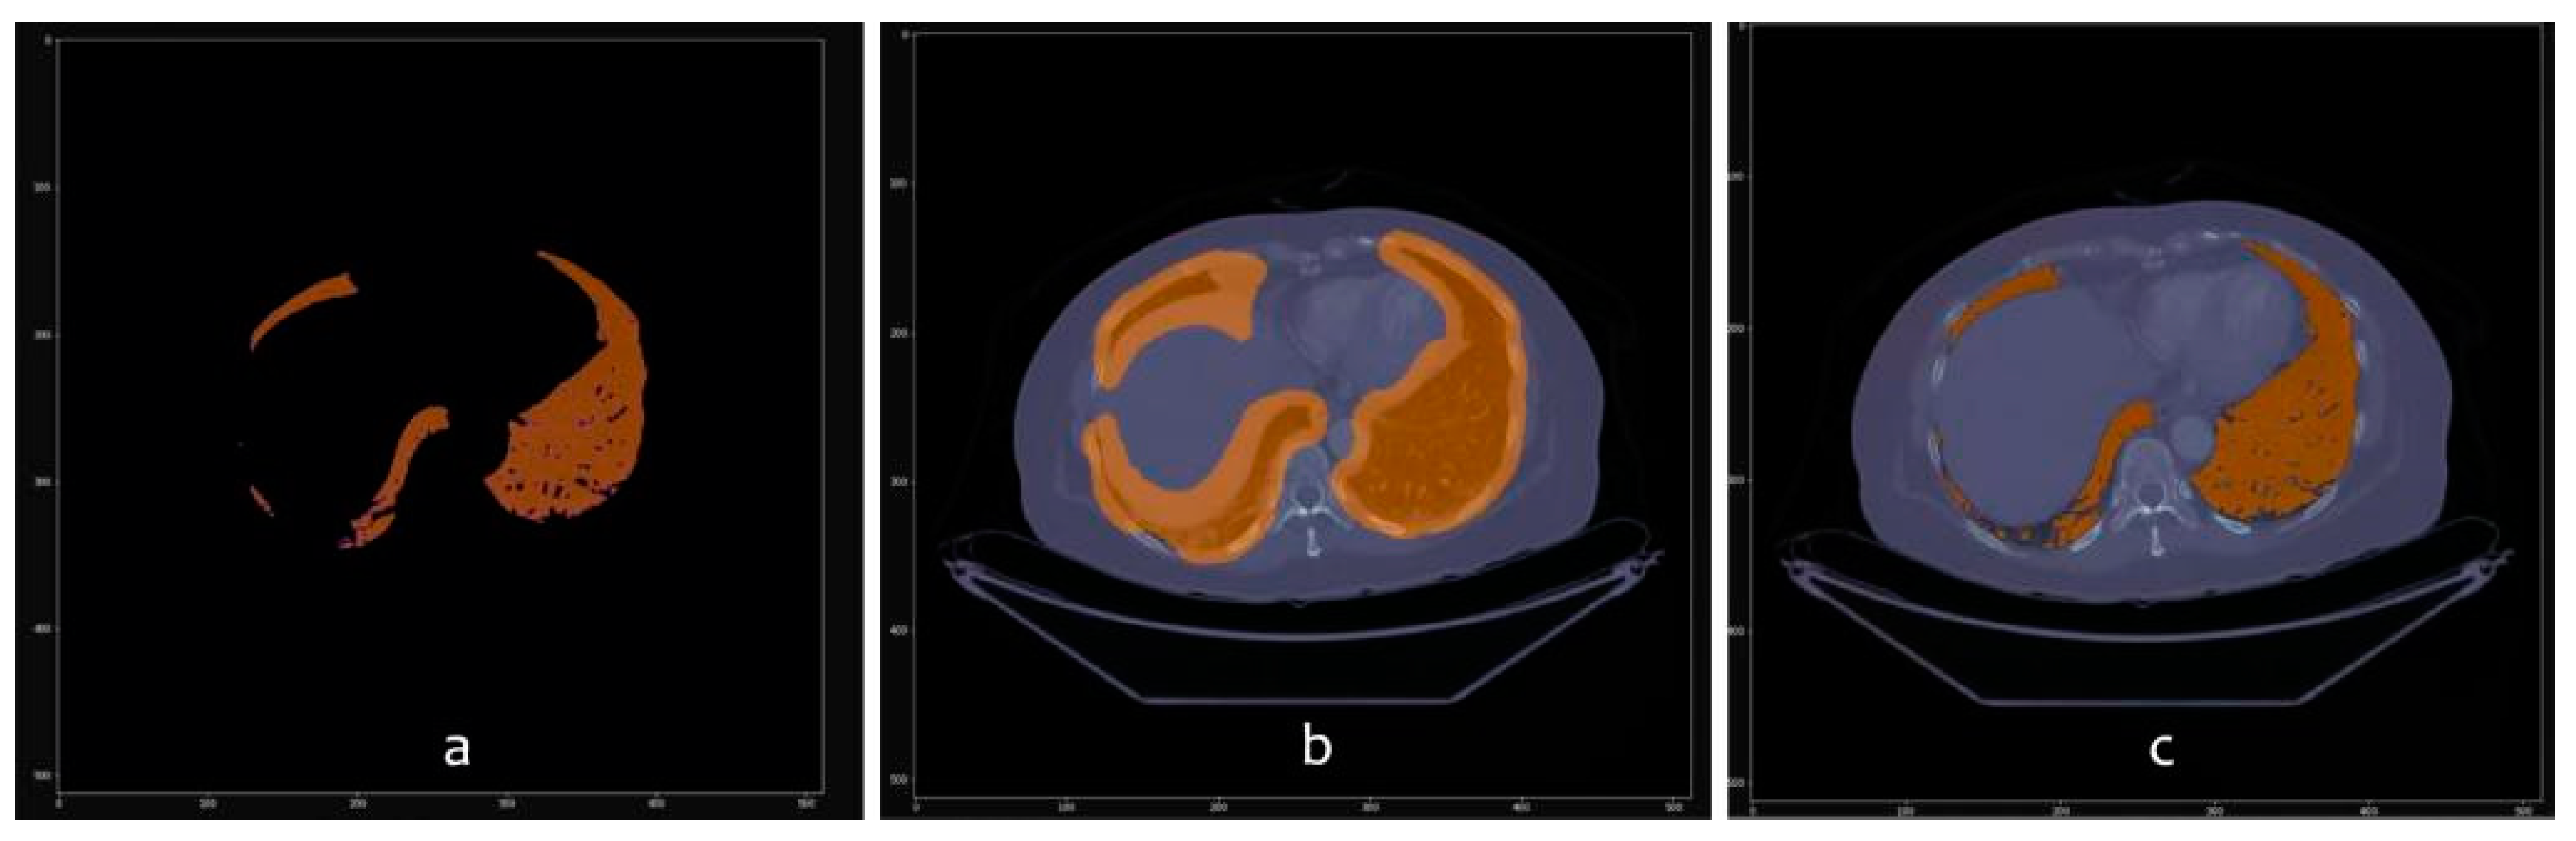

3.1. From dicom to 3D Models with Automatic Segmentation

3.2. Results Visualization